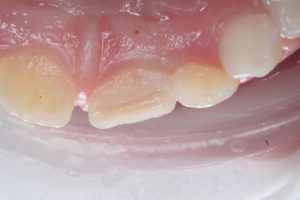

Реставрация зубов в Харькове (клинический случай)

Пациентка 8 лет. Травматический скол центрального резца верхней челюсти.

Лабораторый этап: зготовление «воскового шаблона» на гипсовой модели.

Окончательный вид реставрации.

Клиника Ортокон Плюс предоставляет услуги терапевтической стоматологии по реставрации зубов в Харькове.